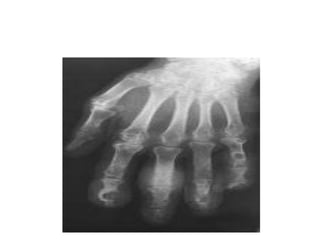

Radio: géodes arrondies ou oval,juxta-artic ou

rompant parfois la corticale osseuse avec

réaction ostéophytique imp(pieds,mains,genoux)

B/L’ arthropathie goutteuse:les dépôts intra-artic d’urate de Na entrainent des destructions ostéo- cartilagineuses des artic atteintes lors des accès aigus Clinique: Dlr mécanique avec raideur et/ou gonfl artic. Des crises aigues peuvent survenir Radio: géodes arrondies ou oval,juxta-artic ou rompant parfois la corticale osseuse avec réaction ostéophytique imp(pieds,mains,genoux)